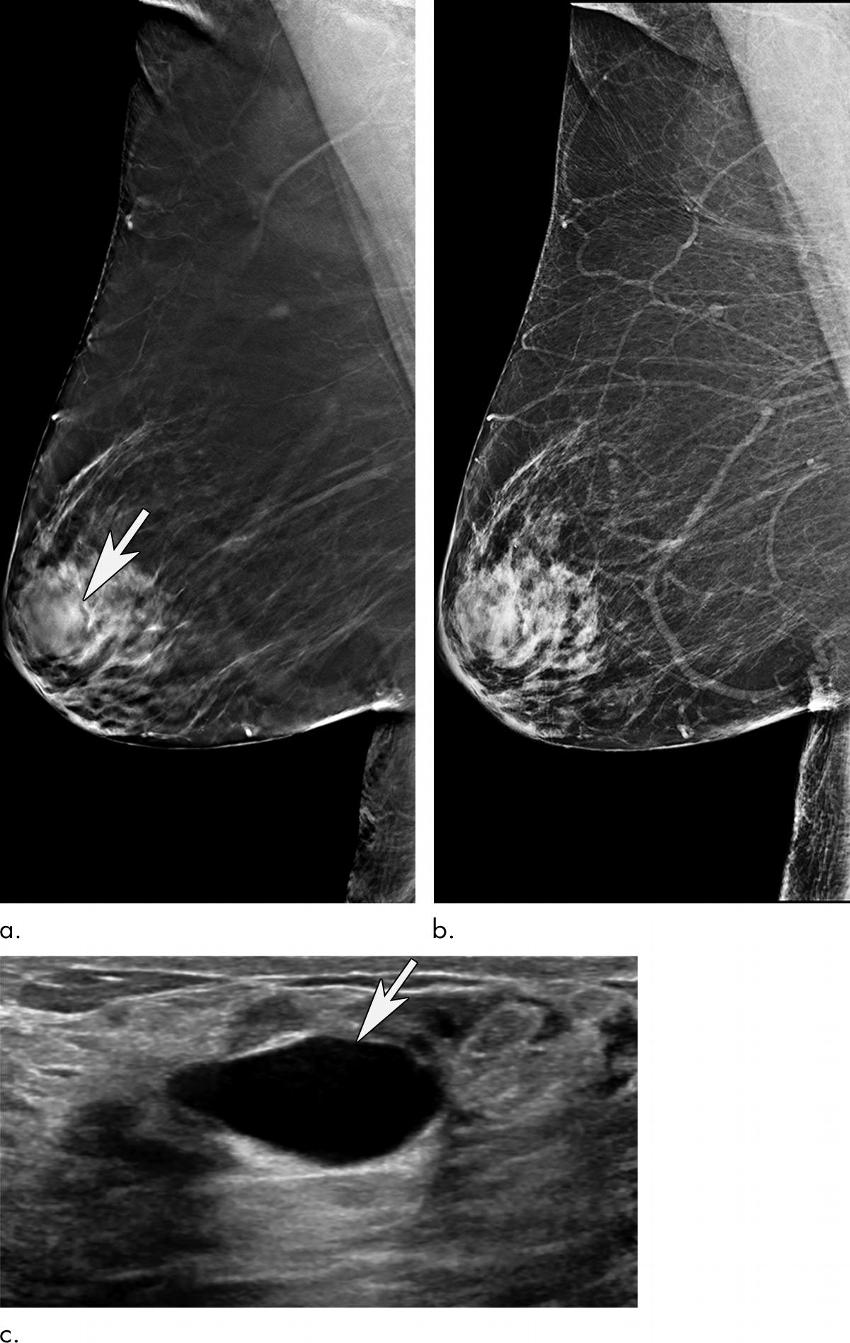

Figure 4. Images in a 70-year-old woman recalled from screening mammography for mass in left breast. (a) Tomosynthesis image from right mediolateral oblique view demonstrates oval mass in superior aspect of right breast at anterior depth (arrow). (b) Finding is not as well demonstrated on two-dimensional right mediolateral oblique view. (c) Diagnostic US demonstrates that mass identified at mammography is simple cyst (arrow). This case is example of false-positive screening examination.